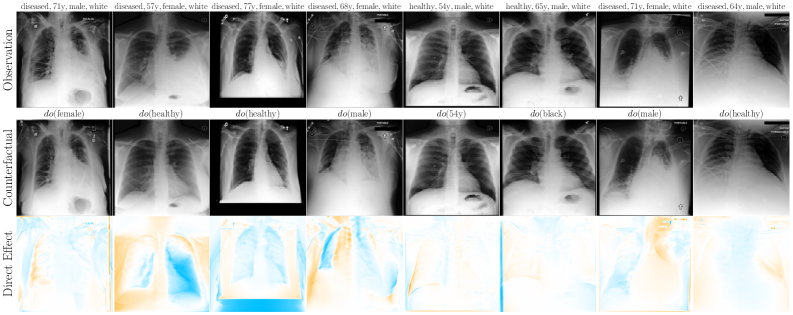

6.2 Case Study: Chest X-ray Imaging Counterfactuals

To extend our study to high-dimensional settings, we conduct experiments on MIMIC-CXR (Johnson et al., 2019), a widely used dataset for counterfactual inference. Our assumed causal graph follows the baselines (Ribeiro et al., 2023; Xia et al., 2024), and includes Sex (), Race (), Age () and Disease () variables, where , and cause the X-ray image . To parameterise our flow models, we use a streamlined version of Dhariwal and Nichol (2021)’s UNet architecture (see Appendix F for details). Table 2 and Figure 4 report our main results. We observe substantial improvements over baselines (Ribeiro et al., 2023; Xia et al., 2024) using our flows, across all three counterfactual soundness axioms, and without requiring any costly counterfactual fine-tuning or classifier(-free) guidance. That said, this alone does not imply causal validity. In Appendix F, we report additional comparisons and ablations. We observe performance trade-offs: for instance, OT-Flow (which assumes Markovianity) outperforms on race interventions but underperforms Flow on disease interventions, suggesting non-Markovian interaction effects or a subpar OT approximation. Notably, our Markovian OT coupling substantially improves over the Naive OT flow baseline.